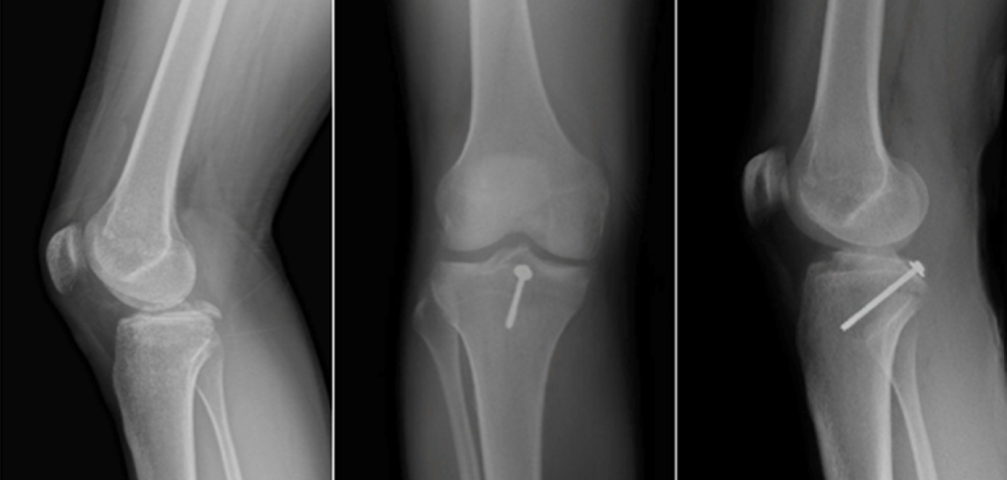

移位的胫骨后叉止点骨折通常需要手术治疗,以恢复后叉韧带张力和膝关节稳定。后叉止点骨折可采用常规切开复位或关节镜下复位固定,对骨科医师来说,关节镜下复位固定存在一定的技术门槛,通常行切开复位治疗。切开复位内固定治疗后叉止点骨折主要有两方面考虑:

显露后复位可采用螺钉或钢板固定。该入路的优势在于:

直视下复位固定,固定疗效确切;